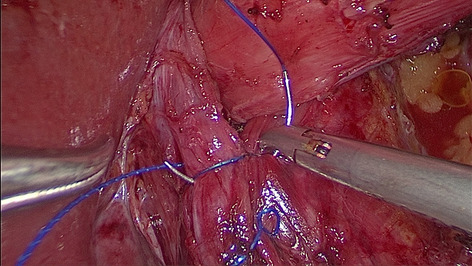

Methods: Starting 01/2019, we implemented a standardized robotic anastomotic technique using a circular stapler and ICG (indocyanine green) for our RAMIE cases at our academic center (Fig. 1). Video material of standardized RAMIE cases was recorded and criteria for selection of suitable videos for annotation were defined. Those included high video quality and performance of a standardized anastomotic phase. Anastomotic phase was defined to begin when the cautery hook touches the esophagus, and the esophagus is divided. Next a monofilament purse string suture is performed robotically. One 12-mm assistant trocar is then removed, and this incision is extended to a mini thoracotomy with a standardized length of 7 cm. The stapler head is inserted and sutured into the esophageal stump using the prepared purse string suture using the robotic instruments. Its end was defined as when the circular stapler head is successfully sutured in and the needle is cut off. Next, video annotation was performed using pixel annotation for tool identification and vector annotation for identification of instrument direction and head of the used instrument (Figs. 2 and 3).

Results: Since 01/2019 a total of 94 RAMIE cases were performed, all cases were set up to be recorded. Successful and complete video recording was found in 60% of cases. N = 15 videos were evaluated for video annotation. 60% (n = 9 videos) were found suitable for annotation as defined above. Reasons for exclusion were failure of standardization of the anastomotic phase such as change of circular stapler size, additional lymphadenectomy, additional swap in the picture, rupture of suture, incomplete video or minor bleeding. Mean time of the anastomotic phase was 27.39 min (range 22.03 min- 30.97 min). The robotically performed part of the anastomotic phase showed a mean of 18.19 min, compared to a mean of. 9.2 min of mini-thoracotomy and stapler head introduction. This leads to a total of 163.72 min of video data suitable for annotation. Interestingly, annotation was found to be more time consuming than previously published as 4 instruments were actively used compared to 2 for e.g. in robotic urological surgery. An average of 6 min per picture were found for pixel annotation, compared to 3 min for vector annotation.